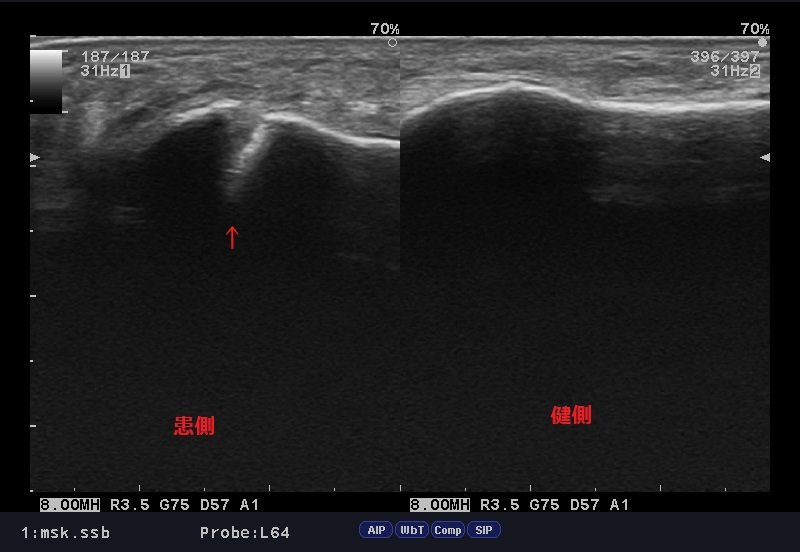

見るからに骨折の可能性が高いですが、確認の為、エコー検査。

中足骨近位端部骨折.jpg

結果、骨折線が確認され「第5中足骨近位端部骨折」と確信。